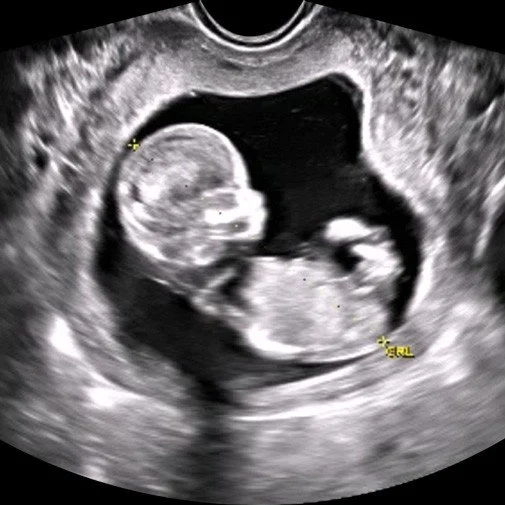

The ultrasound is a powerful tool to determine the viability of the pregnancy, early on before most OB appointments are offered.  The procedures administered at pregnancy centers are limited obstetric ultrasounds that determine three things.

• The location of the pregnancy.  Research suggests in at least 1 out of every 50 pregnancies, the embryo implants somewhere other than the uterus. Most commonly, it implants in a fallopian tube. This type of pregnancy is a tubal or ectopic pregnancy and is life-threatening if not treated.  If not diagnosed early, there is a risk of the tube bursting, internal hemorrhage, and maternal death.

• Gestational age of the baby, or in simpler terms, how far along a woman is in her pregnancy.  The FDA has approved the use of the abortion pill up to 70 days from the first day of your last menstrual period. However, it is very common for the dates determined by the ultrasound to be significantly different from what would be calculated by her LMP. Also, many women have irregular cycles or other medical issues that dis-regulate their menstrual cycle.  If the actual dates are not known before any medical procedure is administered and the pregnancy is outside of the FDA approved window, that can pose great risk to the health of the mother.

• If the pregnancy is viable. Viability means your pregnancy is developing and has a detectable heartbeat. The Mayo Clinic estimates up to 20% of known pregnancies end in a natural miscarriage. The number is likely higher because many women miscarry before realizing they are pregnant.  The pregnancy hormone hCG level, determined by a blood test that some women have to determine pregnancy, stays in the blood and urine for a while after a miscarriage. You can receive a positive pregnancy test when you are no longer pregnant.  So the presence or lack thereof of the heartbeat is definitive of her pregnancy status.

We perform transabdominal and transvaginal ultrasounds.  With a transabdominal ultrasound, I rub a wand-like instrument called a transducer on the abdomen. The transducer picks up the echoes of sound waves and helps me see inside the uterus to learn about the pregnancy.

For a transvaginal ultrasound, the transducer is inserted inside the vagina. This method provides a more detailed image of the uterus, performed if necessary if the findings are limited due to an early gestational age.